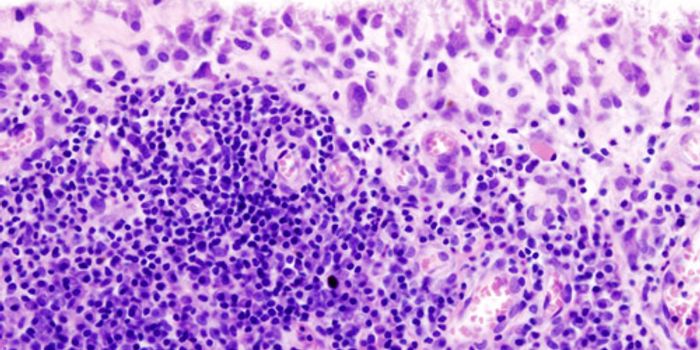

NOV 02, 2015ImmunologyB-cell leukemia occurs in 80-85 percent of children with acute lymphoblastic leukemia (ALL), a fast-growing cancer that ...